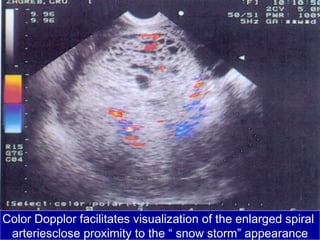

Color Dopplor facilitates visualization of the enlarged spiral

arteriesclose proximity to the “ snow storm” appearance

Color Dopplor facilitatesvisualization of the enlarged spiral arteriesclose proximity to the “ snow storm” appearance